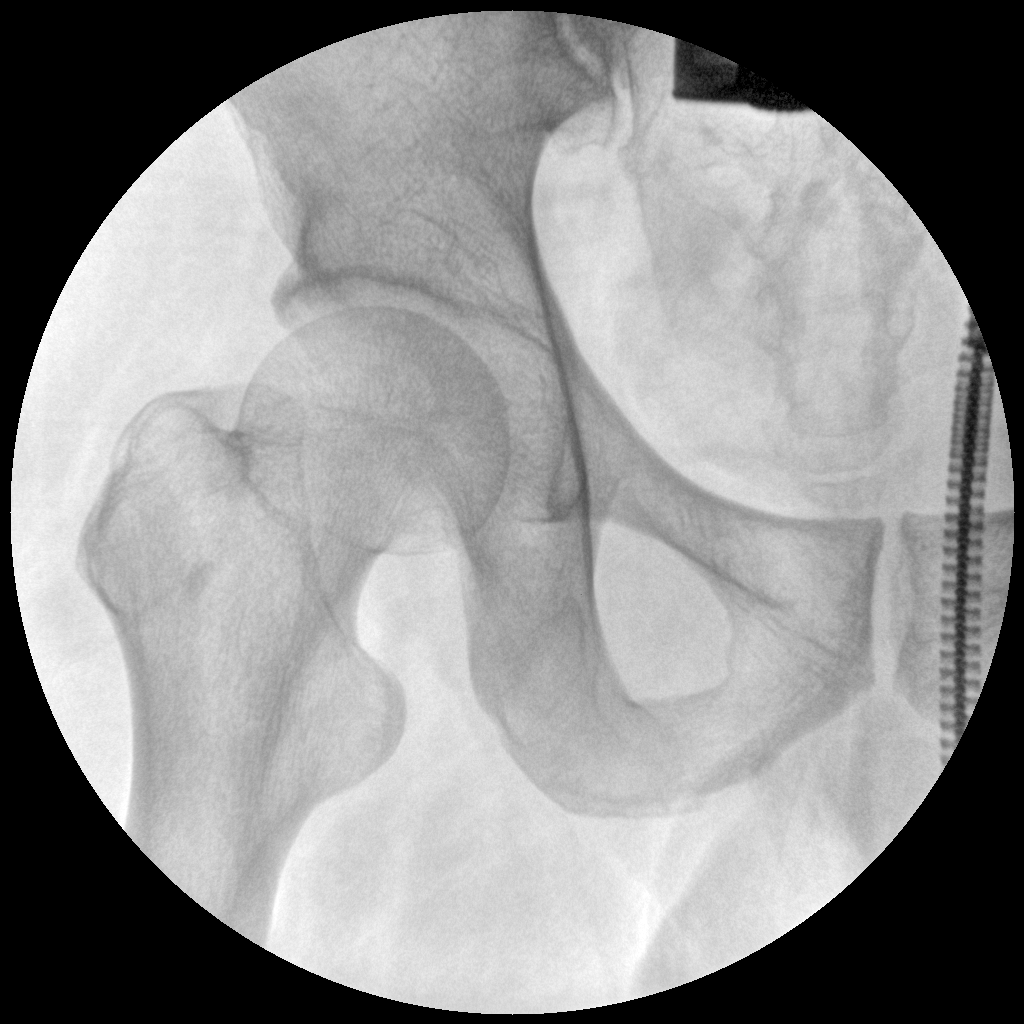

PLX112B 系列高频移动式手术X射线机

●经典影像工作站,可隔室操作避免辐射●全数字化百万像素影像系统,图像清晰●灵活的C臂机架设计,满足临床大范围运动●临床功能丰富,具备脉冲控制、数字摄影、自动透视等●具备手持控制器,远离主机也可自由控制